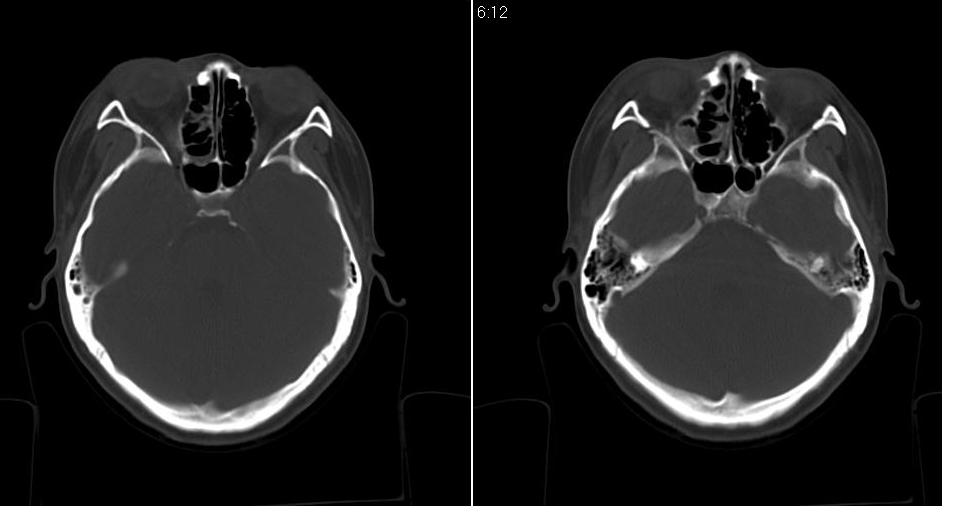

标题: CT9542:鼻窦CT平扫 [打印本页]

标题: CT9542:鼻窦CT平扫

女 18岁,外伤.

右侧上颌窦前壁骨折,窦腔积液.

右侧上颌窦前后壁及右颧骨弓骨折,窦腔积液。

右侧上颌窦前壁、外侧壁骨折,内侧壁可疑骨折,窦腔积液

右侧上颌窦前后壁骨质均不连续,窦腔内见一致性高密度影,右睑部软组织肿胀

1,右上颌窦前后壁骨折,伴窦腔积血可能性大

2,右睑部软组织肿胀

右侧上颌窦前壁、外侧壁、内侧壁骨折,伴窦腔积液;右侧颧弓骨折。

1 、 右侧上颌窦前壁、外侧壁、内侧壁骨折并窦腔积液(血);右侧上颌窦前壁骨折累及同侧鼻泪管;

2、右侧颧骨骨折。

右侧上颌窦前后壁及颧弓骨质均不连续,窦腔内见一致性高密度影,右面部及眼睑部软组织肿胀

1,右上颌窦前后壁骨折伴窦腔积血,右侧颧弓骨折.

2,右面部及眼睑部软组织肿胀